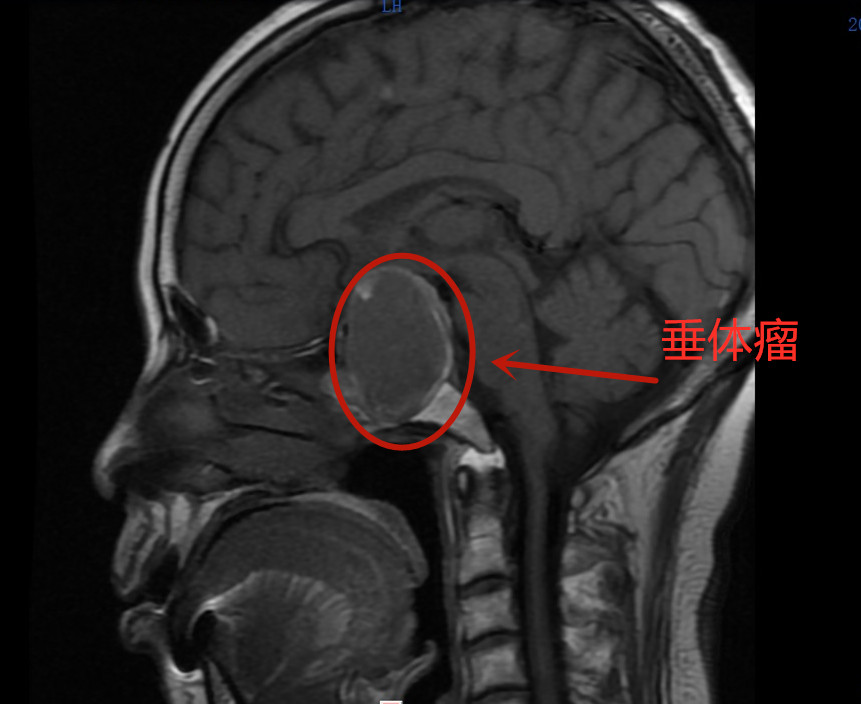

娭毑左眼失明,竟是垂体瘤惹的祸

68岁的唐娭毑在一周前莫名剧烈头痛,第三天竟然左眼失明了,到捷克论坛 一查原来是脑垂体瘤作怪。经过手术治疗,10月12日,唐娭毑已康复出院。

神经外科主任舒毓高和神经外二科主任朱子健得知患者病情后,立即组织人员进行了术前讨论。由于患者鞍区肿瘤约5X5cm,侵犯了双侧海绵窦,压迫了双侧颈内动脉,特别是左侧还压迫了动眼神经,向上压迫了下丘脑及三脑室隐窝,手术风险巨大,术后可能存在各种严重并发症。舒毓高主任表示,患者相信捷克论坛 ,就一定要尽最大的力量帮患者解决问题。入院当晚21时,患者被送入手术室,舒主任带领团队为患者进行切除垂体瘤手术,次日凌晨4时30分手术才结束。术后第一天,唐娭毑激动的握住前来查房的胡林旺副主任医师的手说“我头不疼了,双眼都能看见东西了,而且看的比以前更清楚了,感谢你们。

脑垂体瘤是发生在垂体上的肿瘤,通常又称为垂体腺瘤,是常见的神经内分泌肿瘤之一。它主要分为催乳素腺瘤,生长素腺瘤,促肾上腺皮质素腺瘤等。

舒毓高主任表示,脑垂体瘤属于内分泌系统的肿瘤,当垂体瘤出血,在短时间内会严重压迫视神经,进而会引起视力的突然下降,最终导致失明。据悉,90%以上的脑垂体瘤病人都有视力减退,也可为单眼视力减退,甚至造成一目或双目失明。如果出现莫名的头痛或失明,应及时就医,可以大大提高康复的可能及生命质量。(神经外科  薛智 舒毓高